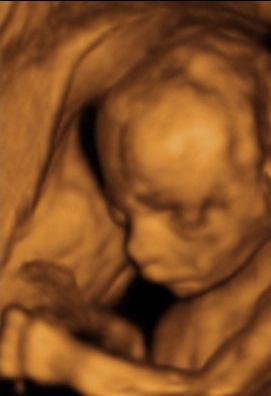

Szintén Lélekszintű kapcsolat alakul ki egy várandós anyuka és magzata között.

„Állítólag a fogantatás lelki töltete meglátszik a gyermeken is”- olvastam a minap Az aranyasszony útja című regényben. Szerintem nem csak a fogantatás lelki töltete látszik meg a gyermeken, hanem a várandós időszaké, a születésé is. Ennek a gyönyörű időszaknak szintén megemelhetjük a rezgésszintjét, és ezzel nemcsak magzatunknak, hanem önmagunknak és a családunknak is jót teszünk.